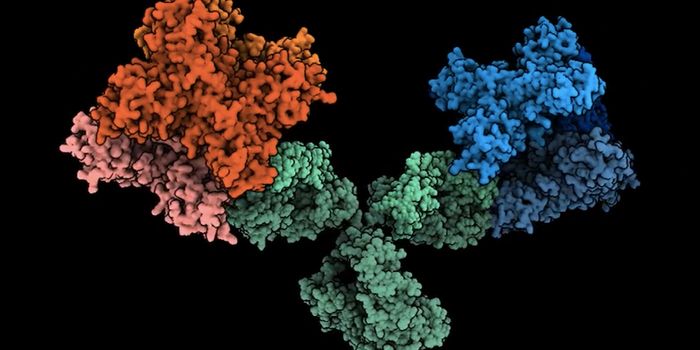

JAN 13, 2022ImmunologyAntibodies are a core part of the immune system's pathogen-fighting arsenal, defending the body against bacte ...